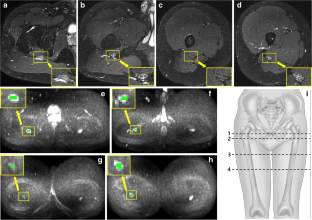

This prospective comparison study included 18 CMT type I patients and 18 age/sex-matched volunteers. Magnetic resonance imaging including DTI and axial T2-weighted Dixon sequence was performed for each subject. Region of interest analysis was independently performed by two radiologists on each side of the sciatic nerve at four levels: hamstring tendon origin (level 1), lesser trochanter of the femur (level 2), gluteus maximus tendon insertion (level 3), and mid-femur (level 4). Fractional anisotropy (FA), mean diffusivity (MD), axial diffusivity (AD), and radial diffusivity (RD) were calculated. The CSA of the sciatic nerve bundle was measured using axial water-only image at each level. Comparisons of DTI parameters between the two groups were performed using the two-sample t test and Mann–Whitney U test. Interobserver agreement analysis was also conducted.

Interobserver agreement was excellent for all DTI parameter analyses. FA was significantly lower at all four levels in CMT patients than controls. RD, MD, and CSA were significantly higher at all four levels in CMT patients. AD was significantly higher at level 2 in CMT patients.